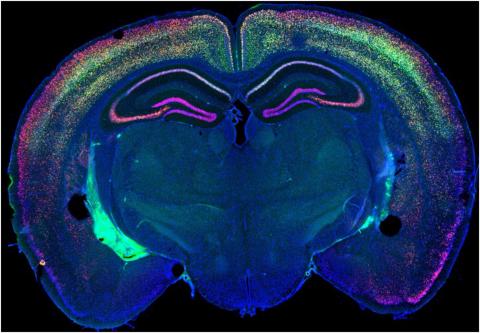

To track these patterns, Abel and his colleagues used a technique called spatial transcriptomics, a method that allows scientists to see and map all the gene activity in a piece of tissue. In Abel’s study, the team added a slice of mouse brain on a slide and marked each slide with dots to create a kind of map.

“Those dots have a molecular marker, and there are about a thousand dots that half of a mouse brain would sit on, and each of those thousand dots is a different marker,” Abel says. “You can identify where different genes are expressed along the brain. In each dot, you’re recording the expression of 3,000 to 5,000 genes.”

In the photos below...

Sleep deprivation leads to an increase in expression of a number of genes in the hippocampus, including a gene called Arc. Below is a set of five images that depict the following. When a non-sleep-deprived brain (B) is compared to a sleep-deprived brain (C) and analyzed statistically (D), this increase in Arc levels can be demonstrated visually, shown here in red. Levels of Arc can be studied at the cellular level, using a technique called RNAScope. These levels, represented by red dots, are low when animals are sleeping (E) and increase when animals are kept awake (F).

What they learned is that each brain region has its own specific molecular fingerprint of the effects of wakefulness and sleep, Abel says.